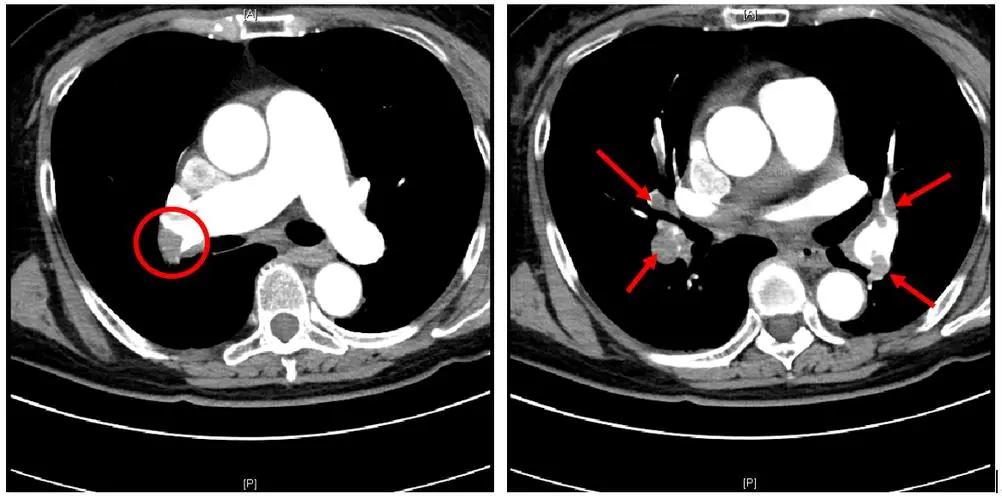

无奈之下,医生就给田女士 做了心电图、心脏彩超然后又补充了肺部CT检查,这次的检查结果就严重多了,田女士的心电图显示T波发生了改变,而且右肺下叶有实变影,胸腔积液引起了不是那么严重的肺不张。

心脏彩超提示田女士的 心脏左室增大,肺动脉内径变宽,三尖瓣有反流 。

心内科医生看完后表示:“这很不正常,胸腔积水的性质查了吗?如果胸水没问题的话我估计就是肺栓塞了”。

经过会诊,大家一致认为这是 肺栓塞导致的 。

立即安排 肺动脉造影 。

终于水落石出!肺动脉造影提示田女士的 肺动脉主干出现了不完全栓塞,右下肺动脉栓塞严重,医生按照经验又给田女士做了双下肢的血管彩超,未发现明显的血栓,排除了双下肢静脉血栓的问题。